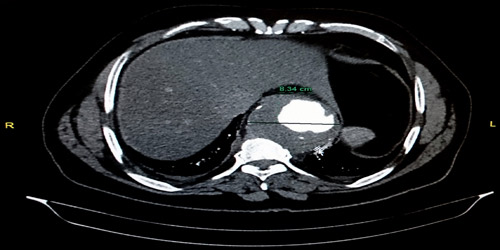

وأوضح الدكتور عويد بن محمد الشمري استشاري أمراض القلب والأوعية الدموية بالمستشفى والحاصل على البورد الأمريكي أنه تم استقبال المريض وهو يعاني من آلام مزمنة وشديدة جداً بالبطن، حيث تم إخضاعه للتصوير المقطعي CT scan angio والتي أظهرت وجود توسع شديد في الشريان الأورطي الصدري، جعل قطره يصل لأكثر من 8 سم بالرغم من أنه في الحالات الطبيعية لا يتجاوز 3 سم، إضافة إلى وجود تخثر في الدم على جدار هذا الشريان نتج عنه جلطات صغيرة أدت إلى سد الشرايين الصغرى بالبطن مسببة الآلام المزمنة التي كان يشتكي منها المصاب عند قدومه للمستشفى.

ونوّه د.الشمري إلى أن الدراسات العالمية تؤكد ضرورة إجراء التدخل الجراحي لإصلاح هذا الشريان إذا بلغ قطره 6 سم لتجنب انفجاره وحدوث وفاة للمريض، كما أن وصول اتساع شريان المريض إلى 8 سم زاد من خطورة حالته الصحية.